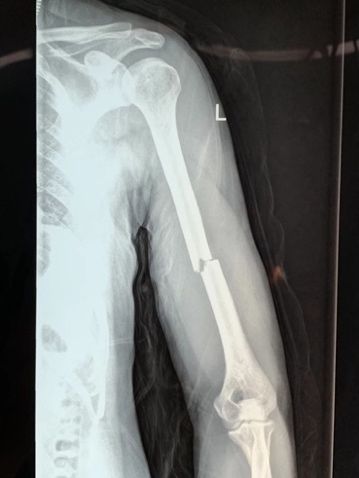

术前X线片